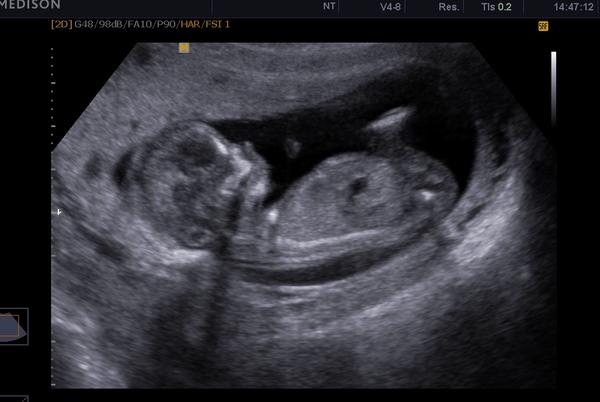

Holky, všem tady přeji nádherně prožité svátky vánoční se svými nejbližšími a v novém roce spoustu těhotných maminek a krásných dětí 🙂 A jak už tady @cermi77 podotkla, tak vánoce jsou časem zázraků, proto bych Vám všem ráda představila naši "asi" slečnu a pokud vše půjde jak má, měla by se narodit v červnu.

Byl to náš poslední mrazáček z 2 IVF, já už opravdu nechtěla, ale teď děkuji dr. Koudelkovi za to, že mě přemluvil a nakonec to vyšlo i navzdory kvalitě embryjka a rodinných okolností, které se u nás udály. Tak mi prosím odpusťte, že jsem tuto zprávu nechala až na dnešek 🙂

@cermi77 😀 za to u tebe jsem to netušila vůbec 😀 Ale hlavně ať je vše na screeningu v pořádku 🙂 Moc se těším na fotečku mimi 🙂 Jinak já byla na screeningu tentokráte ne v prenatalu, ale v reprofitu u dr. Doubka a musím říct, že to je fakt úžasnej člověk. Všechno pomaličku vysvětlil, fotečky a videjka zadarmo. Bohužel ale je tam jen 1x týdně, ale snad se k němu taky vmáčku při sreeningu ve 20tt. Tak šťastný a veselý, ať se tam v bříšku těm naši prckům líbí 😵